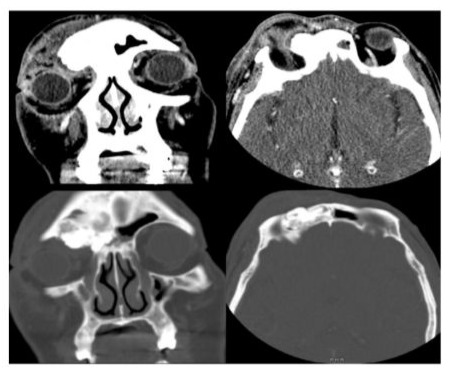

CT showed an osseous lesion occupying the right frontal sinus with extension into the superior aspect of the right orbit and erosion of the right orbital roof. A rim enhancing collection was also noted along the right superior medial orbital roof, which was consistent with subperiosteal abscess (SPA). A radiological diagnosis of frontal sinus osteoma with SPA was made (Figure 1). In view of the rapid drop in visual acuity, red desaturation, raised IOP, increasing proptosis and lid tightness, orbital compartment syndrome was suspected. Urgent right lateral canthotomy was performed by ophthalmologists. There was only slight improvement of symptoms after canthotomy.

Figure 1: Axial and coronal CT scans showing frontal sinus osteoma with SPA